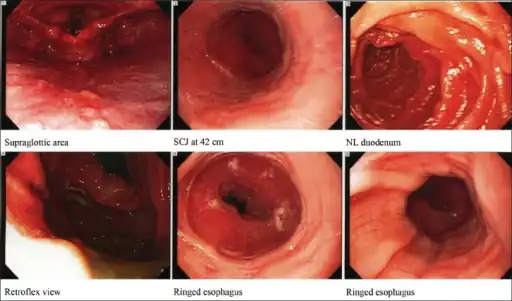

Endoscopy

Endoscopically, ridges, furrows, or rings may be seen in the esophageal wall. Sometimes, multiple rings may occur in the esophagus, leading to the term "corrugated esophagus" or "feline esophagus" due to similarity of the rings to the cat esophagus. Presence of white exudates in esophagus is also suggestive of the diagnosis.[20] On biopsy taken at the time of endoscopy, numerous eosinophils can be seen in the superficial epithelium. A minimum of 15 eosinophils per high-power field are required to make the diagnosis. Eosinophilic inflammation is not limited to the esophagus alone, and does extend through the whole gastrointestinal tract. Profoundly degranulated eosinophils may also be present, as may micro-abscesses and an expansion of the basal layer.[1][17]

-

Concentric rings in the distal esophagus, consistent with eosinophilic esophagitis -

Endoscopic image of esophagus in a case of eosinophilic esophagitis. Concentric rings are termed trachealization of the esophagus. -